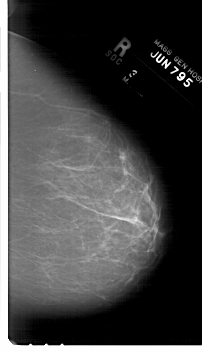

A_1719_1.LEFT_CC

LEFT_CC LINES 6781 PIXELS_PER_LINE 3811 BITS_PER_PIXEL 12 RESOLUTION 43.5 OVERLAY

FILE: A_1719_1.LEFT_CC.OVERLAY

TOTAL_ABNORMALITIES 1

ABNORMALITY 1

LESION_TYPE MASS SHAPE LOBULATED MARGINS MICROLOBULATED

ASSESSMENT 4

SUBTLETY 3

PATHOLOGY BENIGN

TOTAL_OUTLINES 1

BOUNDARY